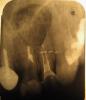

yantr Опубликовано 16 февраля, 2011 Поделиться Опубликовано 16 февраля, 2011 Доброго времени суток, уважаемые специалисты! Помогите,пожалуйста, разобраться в запутанной истории!Ситуация в след. киста была обнаружена давно, не могла решиться на ее удаление, но когда сломала 2-й верх.зуб справа пришлось готовиться к протезированию и соответственно к резекции с удалением кисты. киста верхней челюсти на 1-м и 2-м зубе справа(рис. 1 до лечения)Готовили к операции, распломбировка каналов была сложной,цемент не поддавался, врач использовал бор, и результат был достигнут- каналы были пройдены, канал был запломбирован стеклоиномерным веществом ("Фуджи", насколько я слышала) (рис2- гуттаперчивые штифты?) В 1-й зуб была установлена временная пломба, во 2-й временная коронка. (К сожалению нет снимков с которыми я шла на операцию.)Резекция была проведена, кисту удалили, полость бывшей кисты заполнили костным веществом, положили мембрану. Ретроградное пломбирование не проводилось, насколько я слышала и ощущала.Снимок после операции забрал себе "для истории работ" (цитирую) хирург. Швы сняли, вкладку под коронку устанавлявать сразу не стали, решили подождать, как все приживется и отправили на 3 недели гулять. Прошел месяц я решила протезироваться у другого врача, был сделан снимок (№3 )и что увидели...в канале 2-го зуба отсутствует пломбир.материал и при прохожденнии на верхушке - чувствительность (т.е как я понимаю, канал открыт, сообщается с полостью бывшей кисты. Временная коронка не герметично закрывает канал, шатается!Когда я снова вернулась в клинику, где проходила лечение и проводилась операция, мне было сказано, что пустоты в каналах были оставлены заведомо под штифты и что пломбировоч. материал в апикальной части 2-го зуба продавил доктор, к кот. я обратилась после них??? Что я очень долго где-то ходила, задала им задачу и вообще я могу остаться без переднего зуба! и т.ду меня возникли след вопрсы:1) могли ли при подготовке к операции запломбировать только апикальную часть корня? правильно ли это?2) куда мог исчезнуть пломбировоч. материал из канала зуба (раствориться)?3) не кажется ли вам что резерцированный корень слишком короткий и не подлежит дальнейшему протезированию с учетом того, что его сново придеться пломбировать? 4) на каком этапе.... лечение каналов или резекция могла произойти ошибка?С уважением, к вашему компетентному мнению, очень прошу помочь мне найти ответы на эти вопросы, т.к страдаю из-за этого бессоницей ( как минимум)! Ссылка на комментарий

cassandra Опубликовано 16 февраля, 2011 Поделиться Опубликовано 16 февраля, 2011 (изменено) Причин для волнения нет. все вам сделали правильно1. киста исчезла-это главный плюс2. Если канал пломбировали СИЦ, то на рентгене видно не будет, так как он/ стеклоиономерный цемент/не рентгено контрастный3.2й зуб итак маленький, по анатомии, сплющеный с боков и плохо подходит для штифта. скажите чесно -доктор вам это объясняла, но вы просили все равно попробыватьда еще 3мм должны были как миниум резицировать, скорей всего осталось-13 мм4. на снимке видно что 1и2 зубы подготовлены к штифтованию, и в переапексе все нормально5. То что вам готовы сделатьМТА/ прочный материал/, но он действительно очень дорогойнеобходимости в этом не вижу-ИМХОНе вижу никаких причин , что бы обращаться с претензией, канечно 2й зуб долго не простоит, но вам вероятно и не обещали. Идите к врачу и помогайте ему, а не дергайте, тогда будет вам счастьеВы лукаво не написали в какой клинике вам это делали, в госке или в частной или по ОМСразница между ними есть. Если , что не так прокоментировала-спрашивайтеСлучай ваш рядовой, но зубы падкачали, и скока вам годочков? Изменено 16 февраля, 2011 пользователем cassandra Ссылка на комментарий

yantr Опубликовано 17 февраля, 2011 Автор Поделиться Опубликовано 17 февраля, 2011 Причин для волнения нет. все вам сделали правильно1. киста исчезла-это главный плюс2. Если канал пломбировали СИЦ, то на рентгене видно не будет, так как он/ стеклоиономерный цемент/не рентгено контрастный3.2й зуб итак маленький, по анатомии, сплющеный с боков и плохо подходит для штифта. скажите чесно -доктор вам это объясняла, но вы просили все равно попробыватьда еще 3мм должны были как миниум резицировать, скорей всего осталось-13 мм4. на снимке видно что 1и2 зубы подготовлены к штифтованию, и в переапексе все нормально5. То что вам готовы сделатьМТА/ прочный материал/, но он действительно очень дорогойнеобходимости в этом не вижу-ИМХОНе вижу никаких причин , что бы обращаться с претензией, канечно 2й зуб долго не простоит, но вам вероятно и не обещали. Идите к врачу и помогайте ему, а не дергайте, тогда будет вам счастьеВы лукаво не написали в какой клинике вам это делали, в госке или в частной или по ОМСразница между ними есть. Если , что не так прокоментировала-спрашивайтеСлучай ваш рядовой, но зубы падкачали, и скока вам годочков? 2) тогда что же мы наблюдаем на верхушке канала в 1-ом зубе и жалкие остатки во 2-ом, если не СИЦ? (рис.3) Со слов врача резерцировали 5 мм, но я думаю, вранье все это - все 7 хватанули! 3) говорю честно- никто не говорил мне о их безнадежности!!! единственное предложение от врачей было- поставить коронку не только на 2-й, но и на 1-й ДЛЯ ЭСТЕТИКИ! 4) 1-й я соглашусь нормальный, но во 2-м канал открыт с апикальной и ненадежно прикрыт времен.коронкой с другой стороны. (как считаете, нормально?) 5) то сколько я заплатила за лечение и операцию... в сравнении со стоимостью пломбировки канала "PROROOT" жалкие гроши! А результата нет даже промежуточного! И то что меня снова нагрузят на деньги -это 100%. Меньше всего мне хочеться заниматься претензионной работой! Мне 30-ть лет, я девушка и эстетика для меня важна, как и здоровье в целом! Особенно, когда я оплачиваю и не малые....Начиналось все по ОМС мне пытались пройти каналы, не смогли, заложили какое-то "растворяющее" пломбу вещество...вечером того же дня зуб треснул! Далее я со слезами прибежала в частную клинику и естественно люди спасли, обнадежили и я дергаться не стала и все процедуры решила провести у них. Хотя выглядело все это очень сомнительно...хирурги приходящие в "полночь" в выходной день! Честно скажу- душа не лежала к лечению в данной клинике, но назад дороги не было и сейчас ее нет, я понимаю, это кабала!!!так как если не закончить у них протезироваться, то и обращаться будет некуда, если последствия нежеланные начнутся! Вот такое мне счастье выпало! Ссылка на комментарий